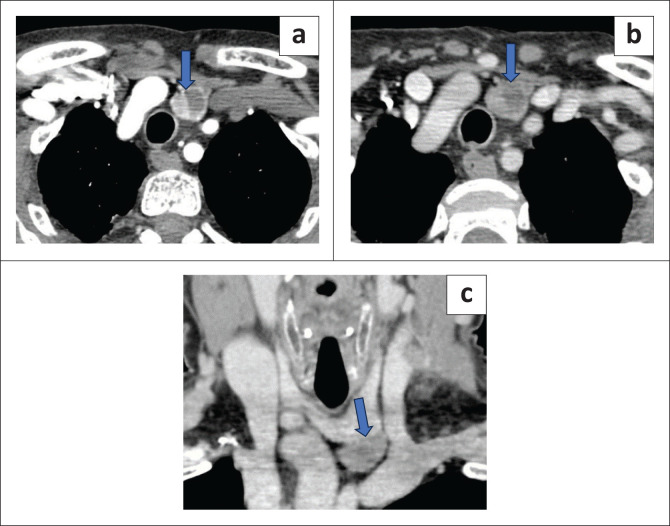

Results: Of the 44 patients who underwent 4DCT, operative findings of three patients were discordant with the 4DCT findings. The calculated sensitivity of 4DCT was 93%. 4DCT was able to identify lesions in ectopic locations in two cases and missed one case in an intra-thyroidal location, misinterpreted as a suspicious thyroid lesion. The sensitivity of 4DCT in detecting multiglandular disease was 75%. Of the diagnosed parathyroid lesions, 52.1% were located on the left, 35.4% on the right and 12.5% were located bilaterally. Additionally, 76% were seen inferiorly and 24% were seen superiorly.

Conclusion: 4DCT has high utility in the presurgical localisation of the eutopically or ectopically placed diseased parathyroid glands in single and multiglandular disease and also provides additional anatomical details.

Contribution: 4DCT identified additional findings such as aberrant origin of right subclavian artery, which is an important pre-operative finding for the surgeon to be aware of. This study contributes to the existing literature on the role of 4DCT.